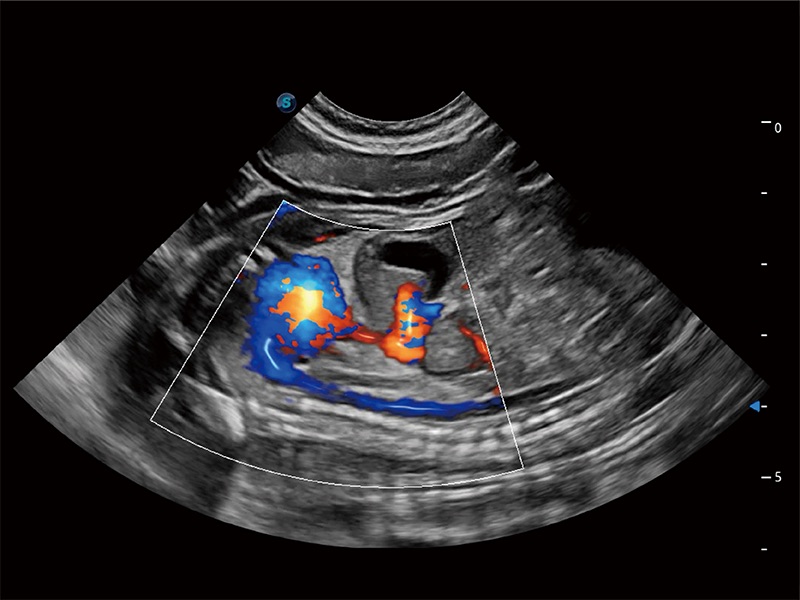

ProPet 80 配備了豐富的心臟探頭群、先進(jìn)的成像技術(shù)和專業(yè)的心臟測(cè)量工具,可幫助動(dòng)物醫(yī)生為不同體型和生理結(jié)構(gòu)的動(dòng)物提供心臟和心肌功能的全面評(píng)估。

實(shí)時(shí)用顏色表示心肌組織運(yùn)動(dòng),觀察和定量組織的運(yùn)動(dòng)情況,對(duì)快速檢測(cè)與評(píng)估心肌的灌注和活性、電傳導(dǎo)及心肌收縮和舒張功能等均能提供重要的診斷信息。